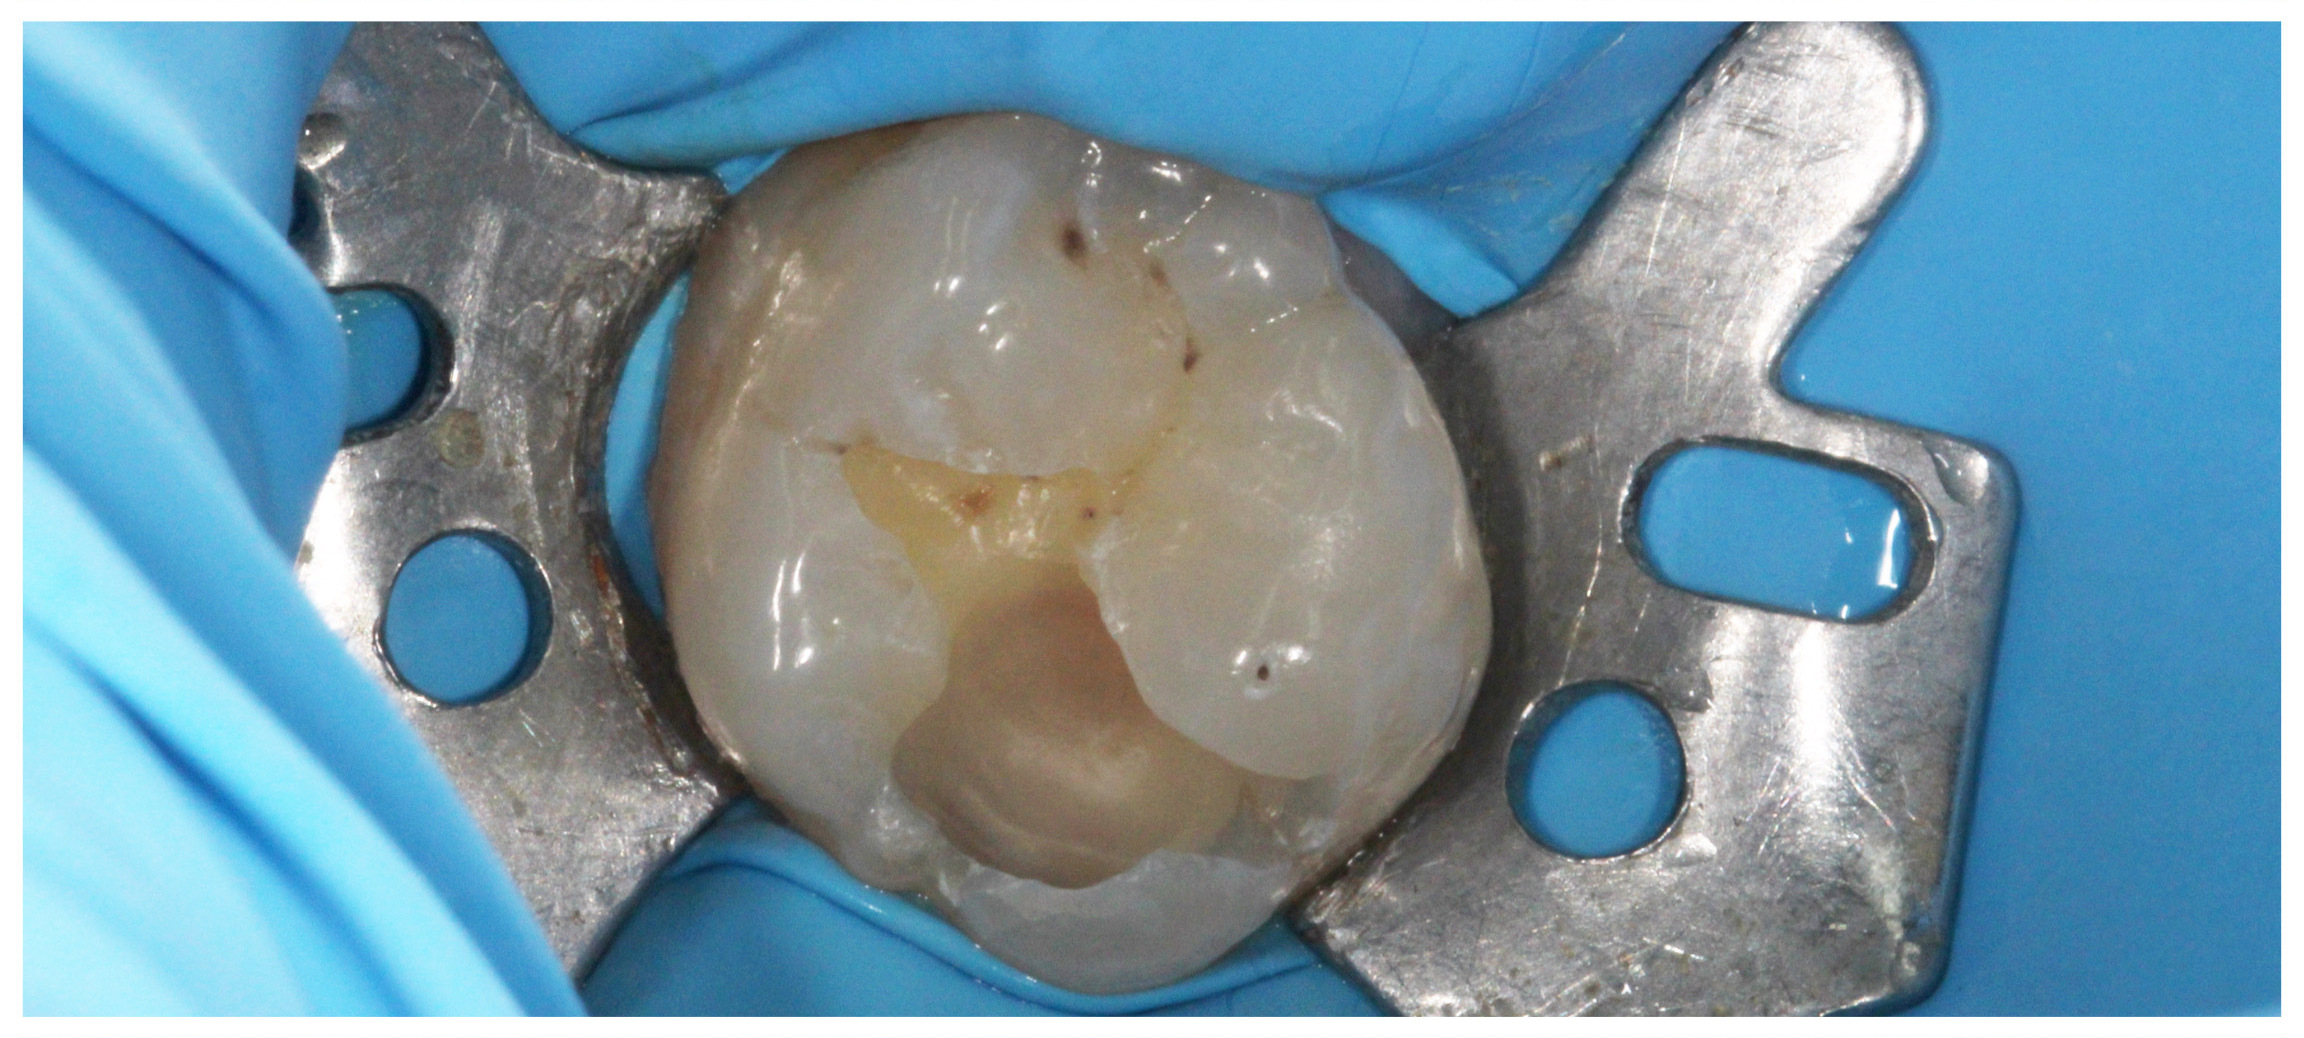

„White“ filling with caries on the first molar, new caries on the second molar

New photocomposite fillings